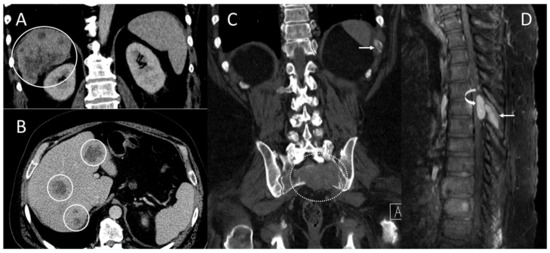

2.1. Patient #1

2.2. Patient #2